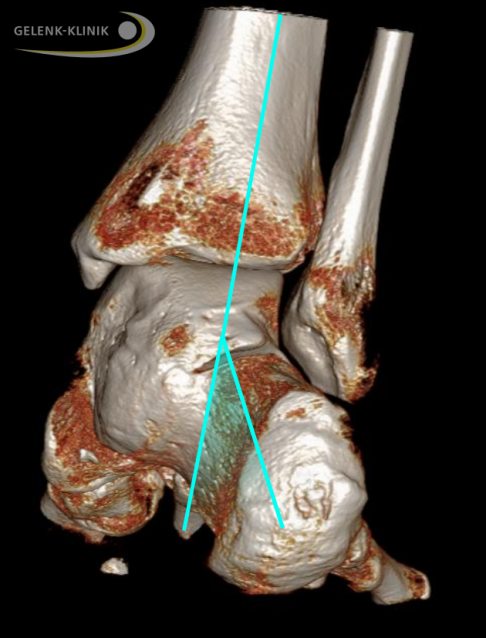

3D-Bildgebung durch DVT unter Belastung bei talocalcanearer Verwachsung: Die Verwachsung zwischen Sprungbein und Fersenbein wird im Detail gezeigt. Die abweichende grüne Linie von der Mittellinie markierte die massive Fehlstellung der Ferse zur anatomisch korrekten Stellung. © Gelenk-Klinik

Die DVT- oder CT-Untersuchungen stellen knöcherne Brücken zwischen den Fußknochen optimal dar. Auch eine bereits eingetretene Arthrose wird mit diesen Untersuchungen erfasst. Mithilfe der DVT unter Belastung des betroffenen Fußes ermittelt der Spezialist die genaue Fußstellung.

Beide Untersuchungen geben detaillierte Informationen zur genauen Lage und zum Ausmaß der Koalition. Im Hinblick auf eine operative Therapie kann der Spezialist mit diesen Befunden die vollständige Resektion der Verwachsung exakt planen.